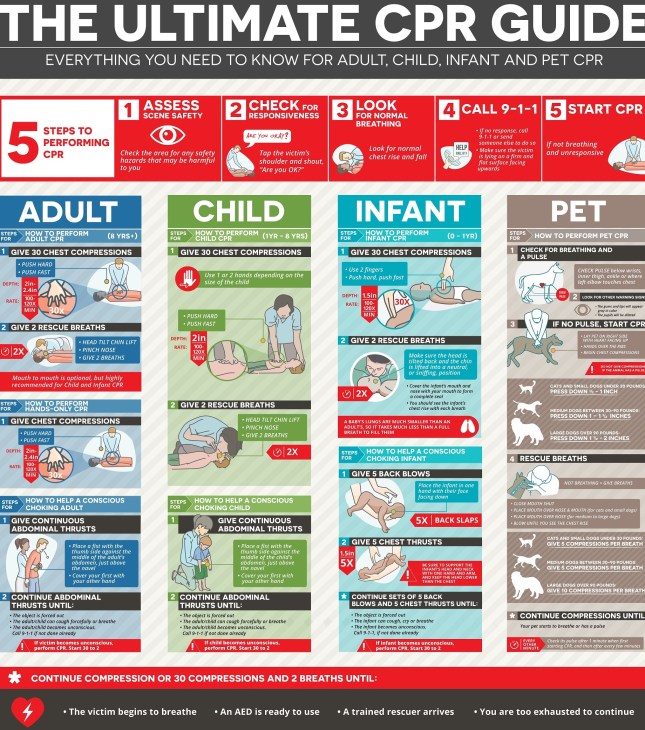

bicycle. Its a very very special journey from a village kid who is Milk Vendor( person who used to sell MILK by going to each house) to Quality Control Manager in London, developing teams, implementing effective QA Practices. Its true. I never feel shy to say where I started and where are my roots are. By considering my current position or traits or appearance, many assume that I am from a High end family, who´s born with Silver spoon. Which is not correct. In each step of my Life I faced obstacles, hurdles, ill-treatments from society for being born in low class, caste family, but I let nothing to distract me from reaching my goals. increasingly common across world. The statistics are indeed worrying; 50% of all the heart attacks in Indians occur under 50 years of age and a quarter of all the heart attacks in Indians occur under 40 years of age, according to the data available with Indian Heart Association.

increasingly common across world. The statistics are indeed worrying; 50% of all the heart attacks in Indians occur under 50 years of age and a quarter of all the heart attacks in Indians occur under 40 years of age, according to the data available with Indian Heart Association.